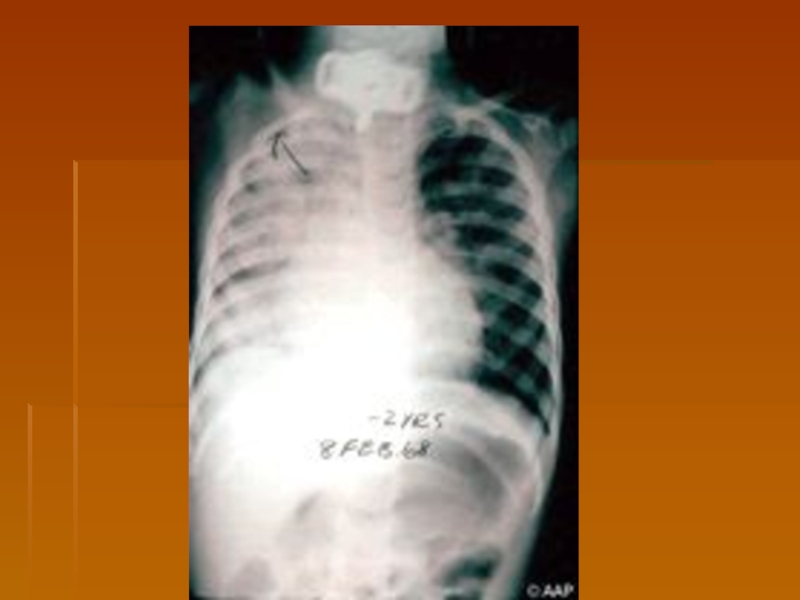

Слайд 19Copyright ©2006 American Academy of Pediatrics

Дифтерия переднего отдела носа